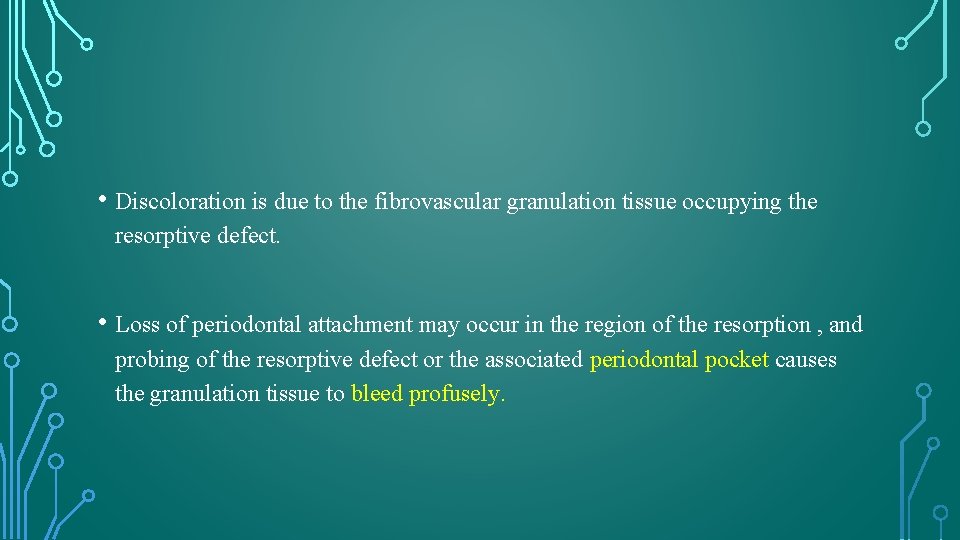

INTERNAL ROOT RESORPTION • Originates in and affects the root canal wall. • It is further classified as either inflammatory or replacement. • The replacement type is associated with the deposition of mineralized tissue in the root canal space after the initial loss of dentin.

HISTOLOGIC APPEARANCE • Pulpal tissue was populated to varying degrees in all teeth with an inflammatory infiltrate composed predominantly of lymphocytes and macrophages. • The odontoblast layer and predentin were absent from the affected dentinal walls, which were populated by large, multinucleated odontoclasts occupying resorption lacunae. • Islands of mineralized tissue occupying the root canal space are the defining feature of internal replacement resorption.

RADIOGRAPHIC FEATURES AND DIAGNOSIS • Gartner – radiolucency of uniform density that have a smooth outline and are symmetrically distributed over the root of the affected tooth • The outline of the root canal wall should not be traceable through the resorption defect because the root canal wall balloons out. • Oval, circumscribed radiolucency in continuity with the root canal wall. • Internal replacement root resorption – somewhat mottled or clouded appearance as a result of the radiopaque nature of the calcified material occupying the lesion.